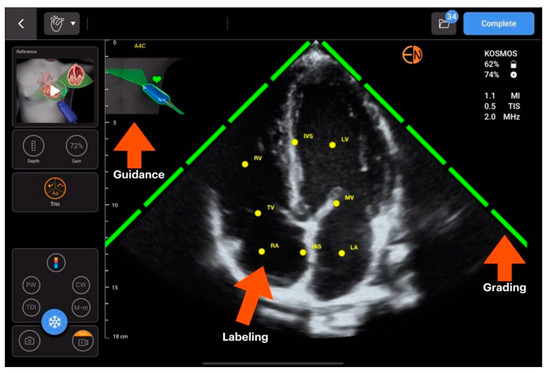

| SmartEchoVue | Mindray | assessment of views | Whole body |

| Us2.ai and AI TRO | EchoNous | ||

| Butterfly ScanLab | Butterfly Network | ||

| LVivo Seamless | Philips | ||